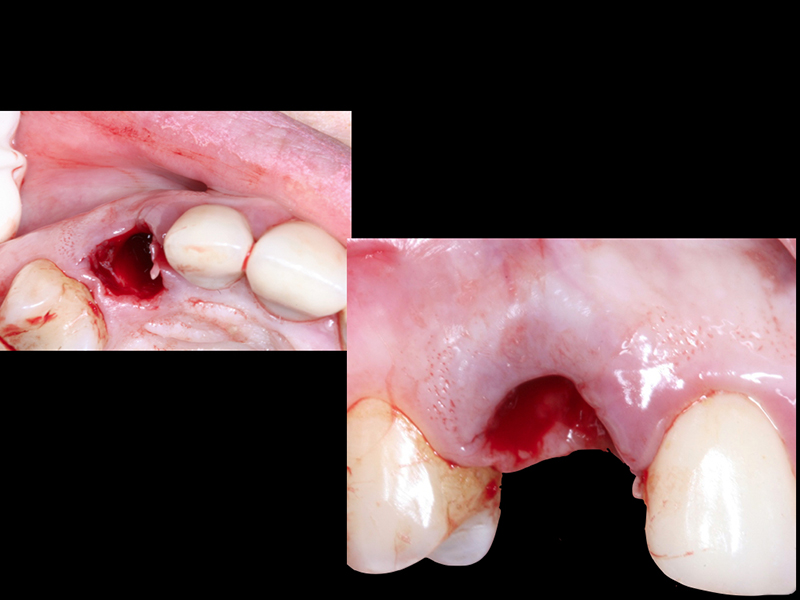

- Cirurgia de Instalação dos Implantes: Os implantes são fixados no osso maxilar ou mandibular, proporcionando uma base sólida para a prótese.

- Fixação da Prótese: Em até 72 horas após a cirurgia, a prótese provisória é instalada, permitindo que o paciente recupere a funcionalidade e a estética imediatamente.